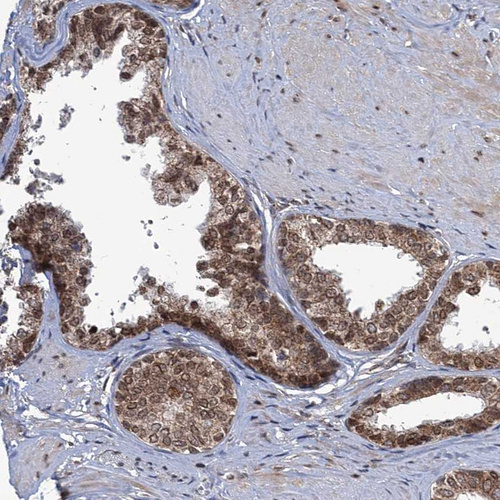

Immunohistochemical staining of human lymph node shows strong nuclear positivity in non-germinal center cells.